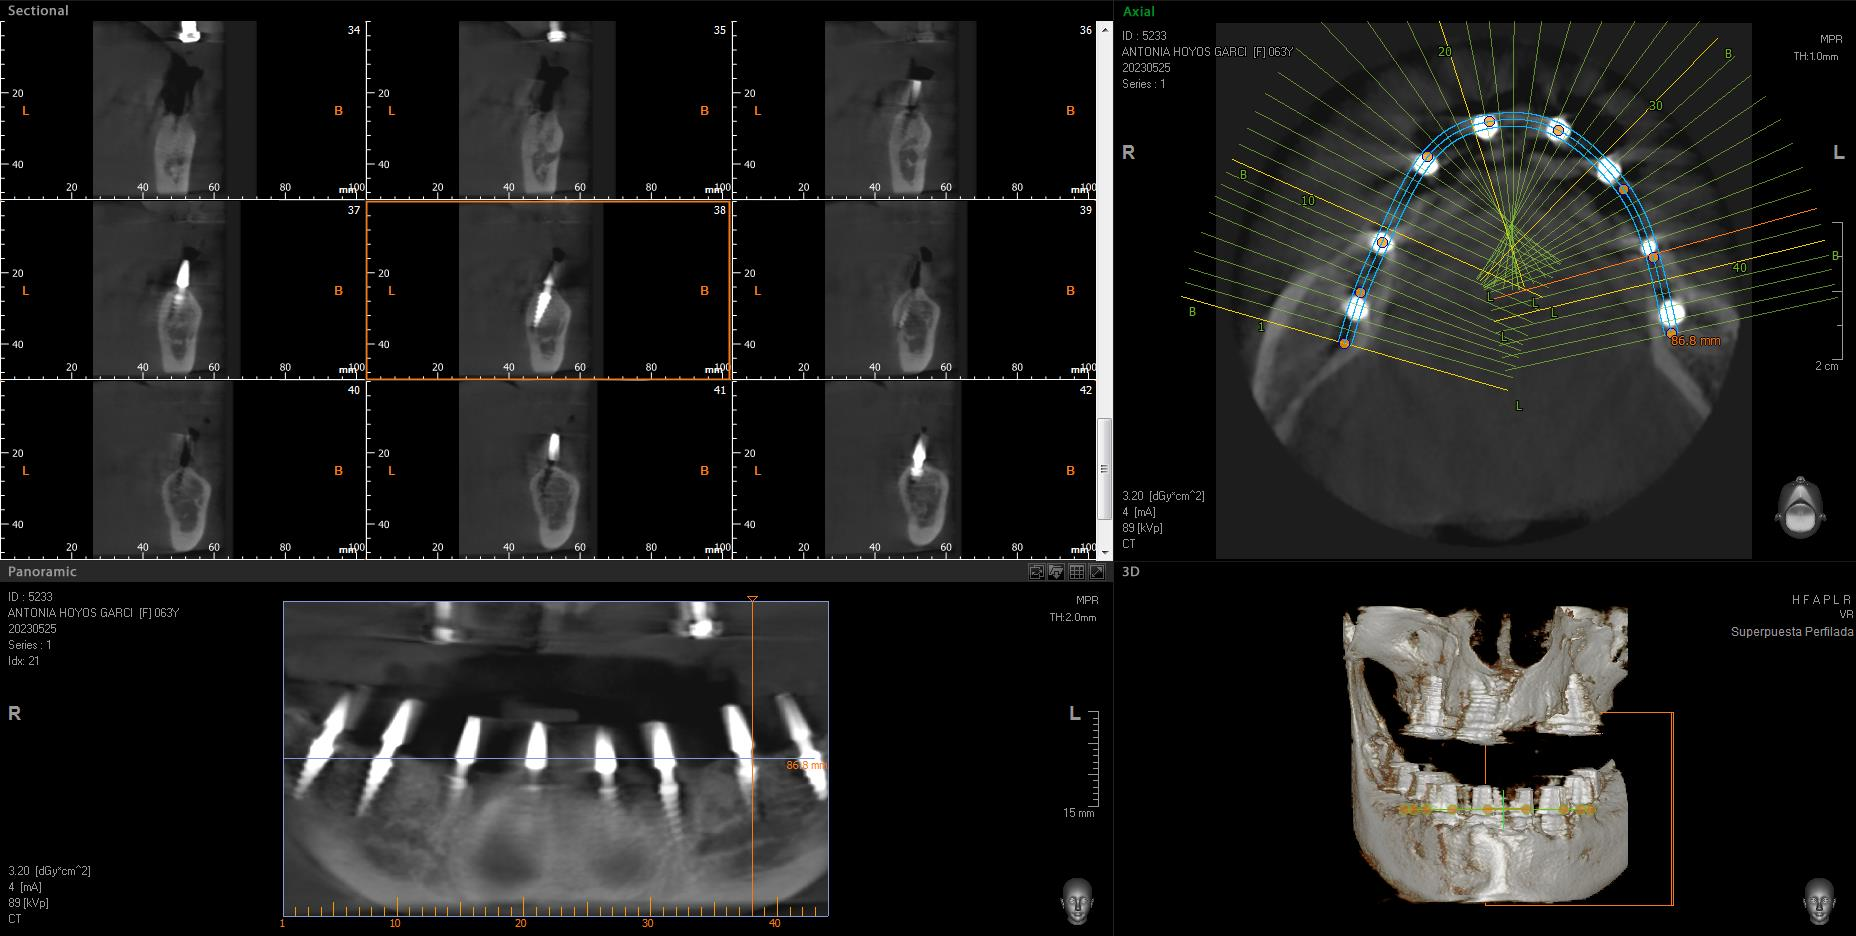

Implantes SLD-c

Secuencia de imágenes RX, antes y después de la inserción de implantes SLD-c en la parte inferior de la boca.

Paciente mujer de 65 años.

- Radiografía previa a la operación.

- Colocación implantes Radhex SLD-c parte inferior.

- Colocación implantes Radhex SLD-c parte inferior con soldadura.